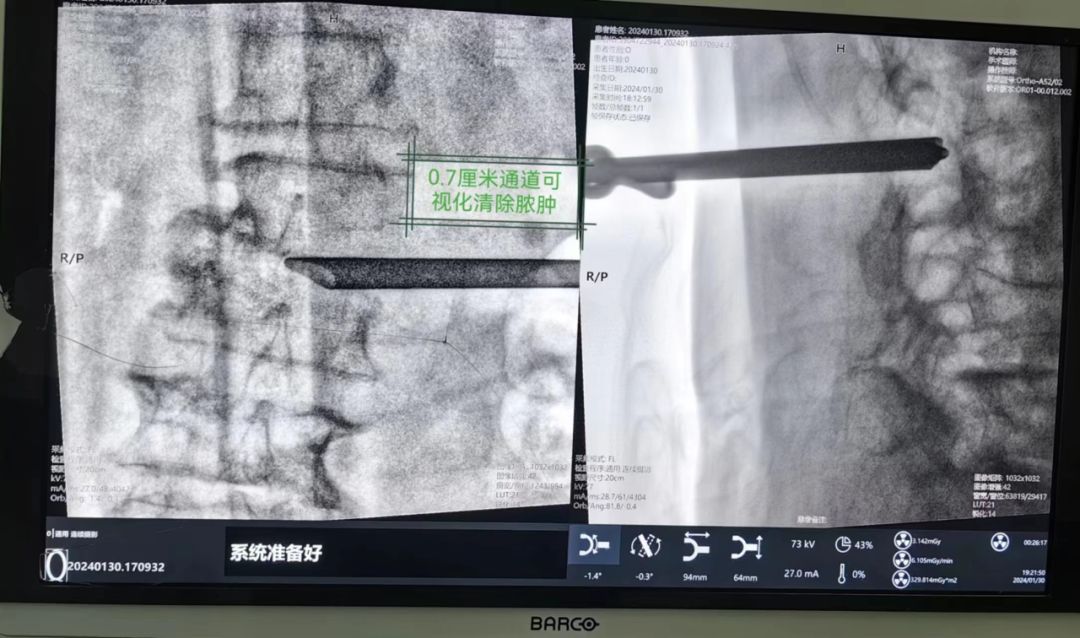

术前 因患者高龄且身体情况较差,传统的开放手术清理脓肿风险极大,需要剥离大量的腰背肌肌肉止点,创伤较大,出血较多。骨科主任袁志峰、主治医师吴锦华等团队综合考虑患者病史,决定给予患者实施“椎间孔镜脓肿清除+置管引流”手术。 在与患者及家属进行充分的沟通及术前准备后,1月30日,骨科手术团队在麻醉科的支持下,耗时1小时,成功为高龄患者开展了微创手术,并通过置管引流将脓肿排出体外,以达到清除感染灶、控制感染扩散的目的。术后,下肢疼痛得到有效缓解。 术中 术后 什么是腰椎脓肿? 腰椎脓肿是主要是腰椎部位发生了细菌感染的现象,这种细菌在腰椎部生长发育,然后随着身体抵抗力的增加,就会将这些细胞包裹起来,如果患者没有出现明显的腰椎部的疼痛,不影响正常的腰部负重活动,但如若腰部出现了脓肿,脓肿比较大,并且导致了腰有明显的疼痛,则需要通过手术治疗。 很多人对于腰痛也习以为常,觉得只要注意休息就可以缓解,有些朋友认为腰痛的原因是腰肌劳损或者是腰椎间盘突出,甚至很多人以为是腰椎间盘突出,但治了一大圈才发现自己患的并非椎间盘突出,而是腰椎脓肿。因此,骨科医师吴锦华表示,腰痛一定要引发重视,及早治疗。 景德镇市第一人民医院骨科的“椎间孔镜下脓肿清理+置管引流”这项新手术具有微创、出血少、创伤小、恢复快的特点,为脊柱感染性疾病的治疗提供了一种新的微创治疗方案,同时拓宽了椎间孔镜技术的适应证,推动了椎间孔镜技术的发展,进一步改善了患者的就医体验。目前景德镇市第一人民医院骨科脊柱学组对于脊柱疾病开展介入治疗、微创治疗、开放手术治疗等多种方式,打造脊柱疾病一体化治疗中心,针对个体差异,提高最适合的治疗方案,给患者最好的治疗方案。